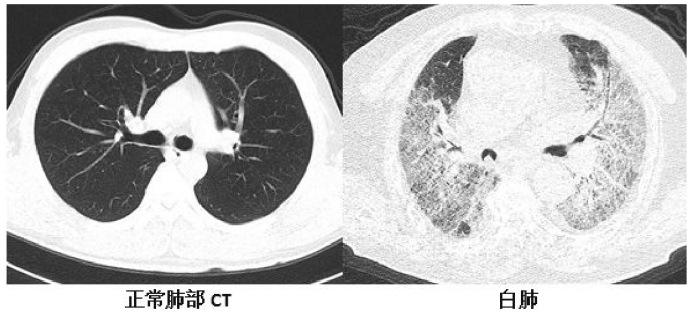

胸部CT检查是诊断肺炎的“金标准”。它能清晰地显示肺部典型的“磨玻璃样”阴影。比X光片要敏感得多。